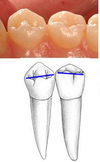

Maxillary buccal view: crown symmetry

Greater symmetry on maxillary 2nd premolar

Maxillary buccal view: occlusal-cervical dimension

Larger on maxillary 1st premolar

Maxillary buccal view: cervical width

Wider cervical neck on maxillary 2nd premolar

Maxillary buccal view: buccal cusp sharpness

Sharper on maxillary 1st premolar

Maxillary buccal view: buccal cusp ridge lengths

Mesial cusp ridge on maxillary 1st premoler is longer

Mesial cusp ridge on maxillary 2nd premolar is shorter

Maxillary buccal view: buccal cusp ridge depressions

More often found on maxillary 1st premolar

Maxillary buccal view: buccal ridge prominence

More prominent on maxillary 1st premolar